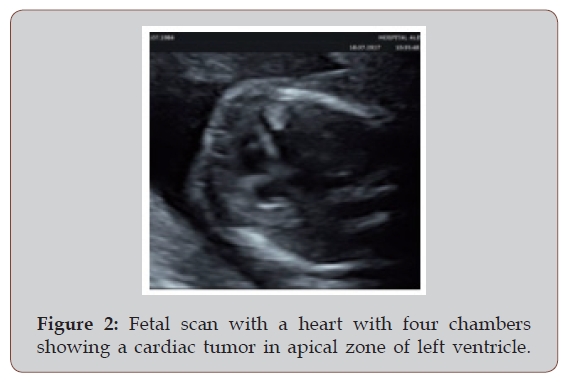

The pregnancy was uneventful, with normal screening 11-14 weeks. She came to prenatal control monthly and a fetal scan was performed at 20 weeks of gestational age. The anatomical measures were normal for gestational age with a male fetus growing in a 75 percentile, normal amniotic fluid. Heart with four chambers and 3 vessels with a homogeneous hiperechogenic focus in left ventricle, apical zone, size 5 x 4 mm with growth toward ventricle cavity, could be a rabdomioma.

A cesarean section was scheduled for 38 weeks because a previous scar. It was delivered a male new born, 2600g, Apgar 8/9 (Figure 1 & Figure 2).